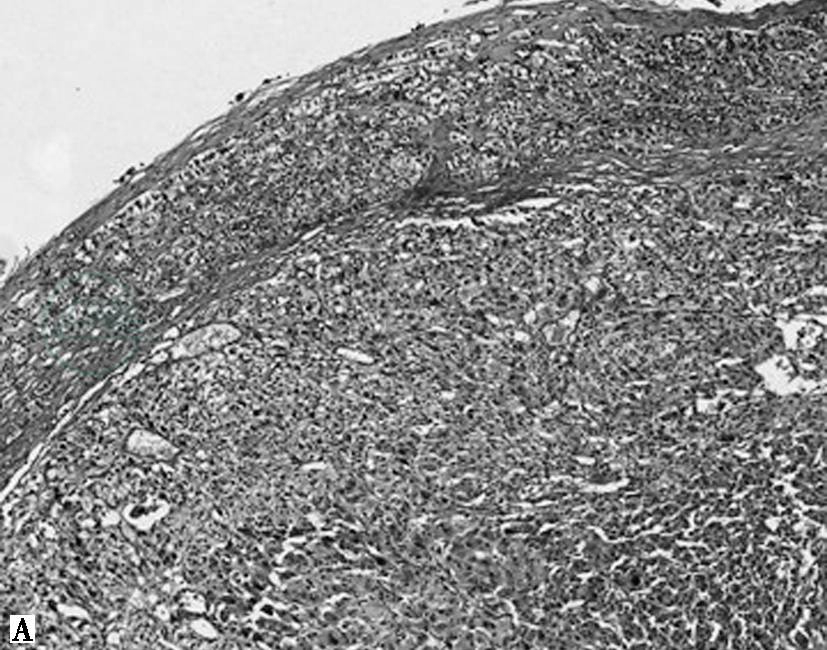

图1嗜铬细胞瘤镜下表现

A.HE 60倍,肿瘤周围见受压的肾上腺皮质;B.HE 100倍,特征性巢状(Zellballen结构),周围包绕纤细的纤维血管性间质;C.HE 200倍,肿瘤细胞形状和大小变化大,嗜碱性或嗜双色性,核仁明显,可见细胞核假包涵体及胞质玻璃样小体;D.HE 200倍,肿瘤细胞多形性及核深染明显,可见胞质内透明小球